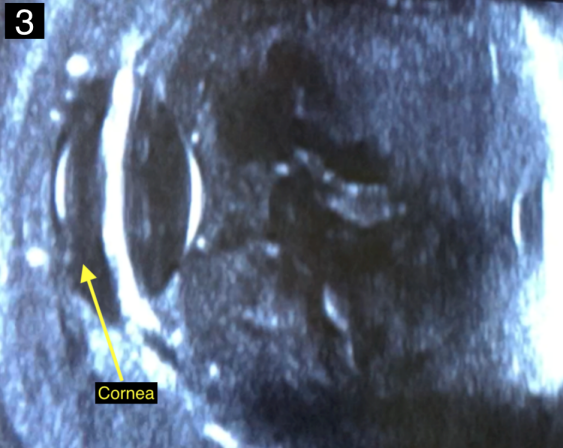

The white blood cell count was 12,800 cells/mm3, blood glucose was 331 mg/dl, and liver transaminases within normal limits. A computed tomography (CT) scan of the orbits showed right-sided orbital cellulitis with significant fat stranding centered around the globe and no significant sinus disease (Figure 2 [Fig. 2]). Ocular ultrasound demonstrated hyperechoic material in the vitreous cavity consistent with vitritis (Figure 3 [Fig. 3]). Abdominal ultrasound revealed mild hepatomegaly without a hepatic abscess.

Figure 3: Ultrasound image of the right eye demonstrating dense hyperechoic cellular debris within the vitreous cavity suggestive of vitritis